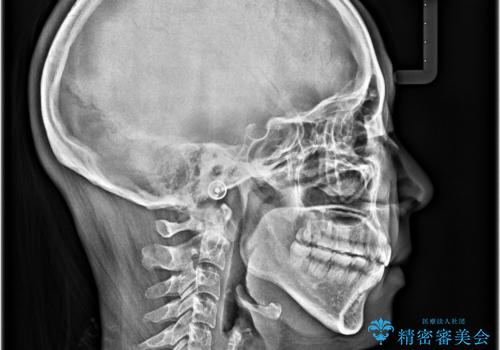

- 前歯が開いて飛び出していることを気にして来院された患者様です。

舌の突出癖により上下前歯は接触できず、更には前方に押し出されて出っ歯になっている状態でした。

上下左右の第一小臼歯4本を抜歯し、ワイヤー装置での抜歯矯正を行っていくのですが、原因である舌の突出癖を改善しないことには治療がうまく進められないため、舌のトレーニングを徹底するよう指導していくこととしました。